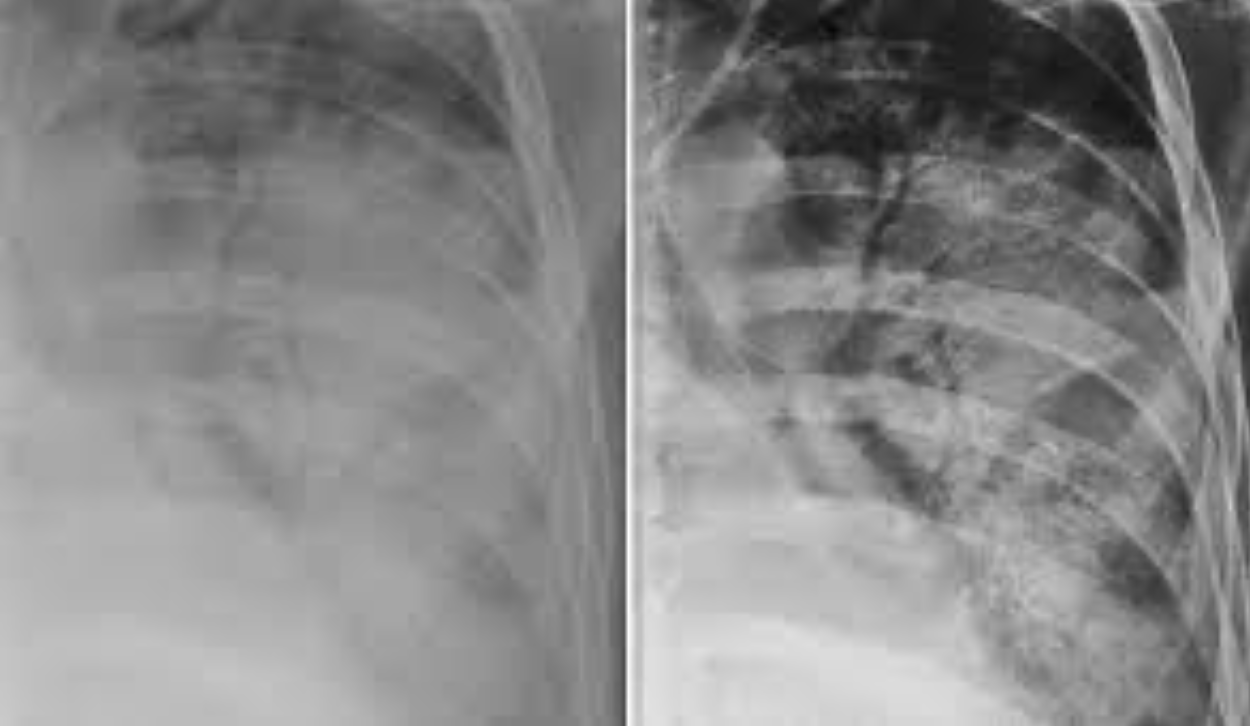

Neumonía bacteriana (radioopacidad)

62

Neumonía lobar (usualmente por S. pneumoniae)